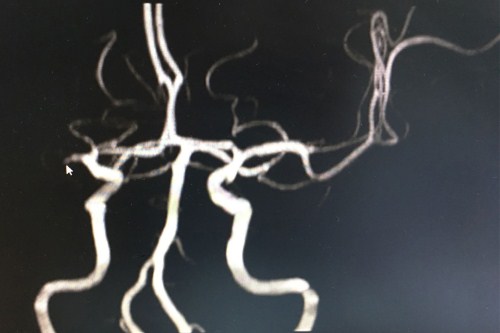

术前血管磁共振:右侧额叶、颞叶及基底节区大片脑梗塞,脑动脉硬化,右侧大脑中动脉闭塞(光标指向处)